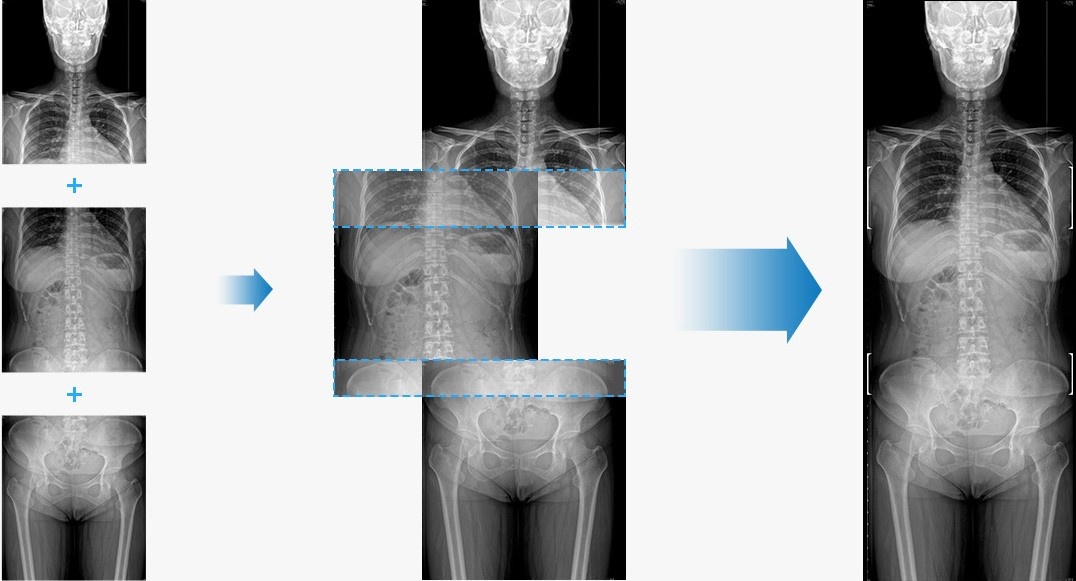

Image stitching plays a crucial role in various medical fields and can enhance the capabilities of healthcare professionals in healthcare and diagnosis. Applications of image stitching include x-ray and MRI imaging, endoscopy and laparoscopy as well as ophthalmology among many others. Some of these application areas are illustrated in Fig. 1-3. Image stitching can assist doctors in various ways. However, a very common use-case is increasing the field-of-view, which is illustrated in Fig. 4. This can find practical applications in many scenarios, such as minimally invasive surgery.